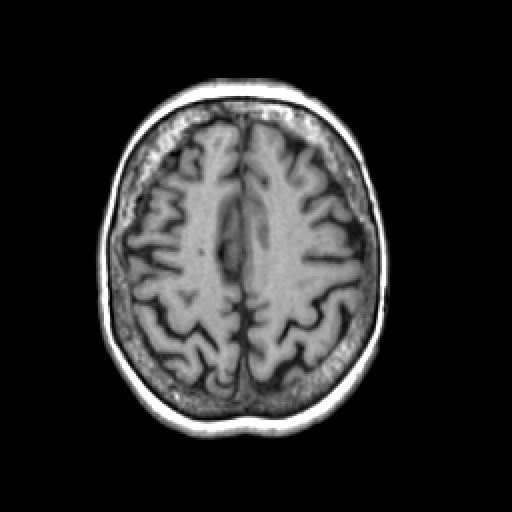

T1-weighted structural MR: Slice 39

Slice 39